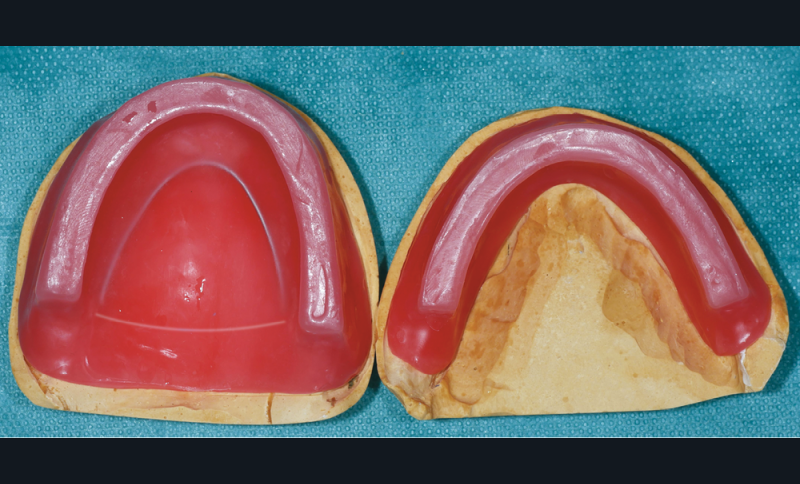

Caractéristiques des maquettes d’occlusion

Elles sont réalisées au laboratoire à partir des modèles issus des empreintes secondaires et doivent être impérativement contrôlées à leur retour du laboratoire. Elles sont constituées d’une plaque base surmontée de bourrelets en cire. Leur étendue et leur volume doivent être le plus proche possible de ceux des prothèses terminées : elles préfigurent ainsi, pour le patient, les prothèses qu’il portera le jour de l’insertion prothétique (fig. 3) [13].

La plaque base doit être rigide, indéformable à température buccale, stable et calibrée [14]. Elle peut être faite en résine ou en cire renforcée par des fils de renfort métalliques. Certains auteurs recommandent l’utilisation de la base définitive en résine acrylique [8,15,16].

Le bourrelet doit être suffisamment rigide, tout en étant aisé à modifier. Il ne doit pas entraver le libre jeu de la musculature périphérique et les organes paraprothétiques (notamment la langue à la mandibule). On peut ainsi utiliser de la pâte de Kerr (marron ou blanche) ou d’un mélange de cire rose et d’une cire plus rigide (type Moyco). Certains auteurs proposent l’emploi d’un matériau thermoplastique type Stent’s afin de conserver une surface occlusale stable [11,17]. Les extrémités postérieures ne doivent recouvrir ni les tubercules rétro-molaires ni les tubérosités, et se terminer par des pans inclinés à 45° (fig. 4).